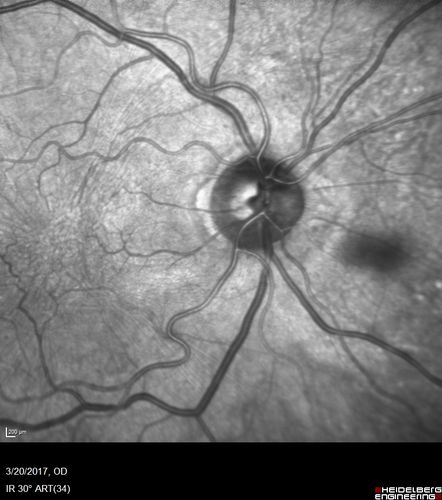

Proliferative Diabetic Retinopathy - NVD regressed with PRP laser

76 year old diabetic man - Presented one year ago with NVD in the left eye.  This regressed with laser but then a year later worsened.  Additional PRP was done and the NVD regressed again.